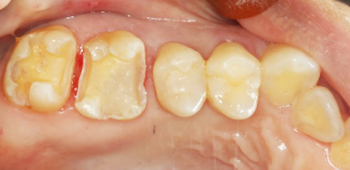

虫歯の治療も現在はセラミックの治療が最も良いとされています。

銀の詰め物と比較して『精度』が良く、再度虫歯になるリスクが低いです。

保険治療で使用されるセメントは熱によって膨張と収縮を繰り返し、長期間の使用により劣化してくることが示唆されています。

その結果内部に隙間ができ0.3㎛の大きさの細菌の侵入を許し虫歯になってしまいます。

当院のセラミック治療は適合も良く、セメントも歯と化学的に接着するものなので細菌の侵入を防ぐことが出来、さらに審美的です。

| 治療期間 | 2週間 |

|---|---|

| 費用 | セラミックインレー 6万6千円(顕微鏡治療の場合10万円) |